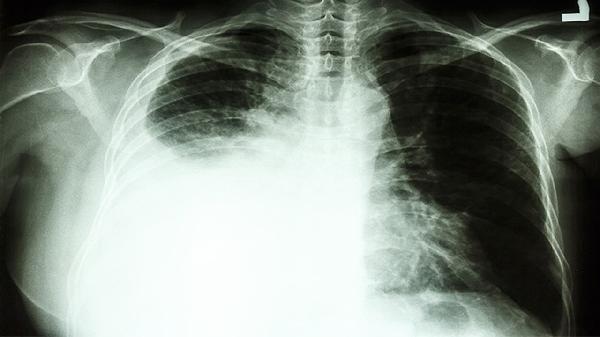

3.化疗与免疫治疗结合可以发挥协同作用。化疗不仅能直接杀灭癌细胞,还能释放肿瘤抗原,增强免疫系统的识别能力。免疫治疗则能延长化疗的效果,减少肿瘤复发风险。例如,在非小细胞肺癌的治疗中,化疗联合PD-1抑制剂显著提高了患者的无进展生存期和总生存期。